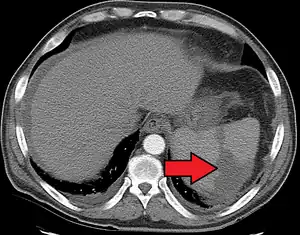

Splenic infarct seen on CT

An abdominal CT scan is the most commonly used modality to confirm the diagnosis,[3] although abdominal ultrasound can also contribute.[16][17][18]